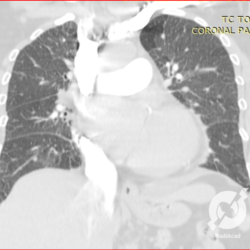

Lesões intersticiais reticulares difusas, aumento do volume cardíaco (Rx)/Opacidades em vidro fosco, espessamento septal e consolidações alveolares difusas, com predomínio peri-hilar bilateral. Edema agudo de pulmão.